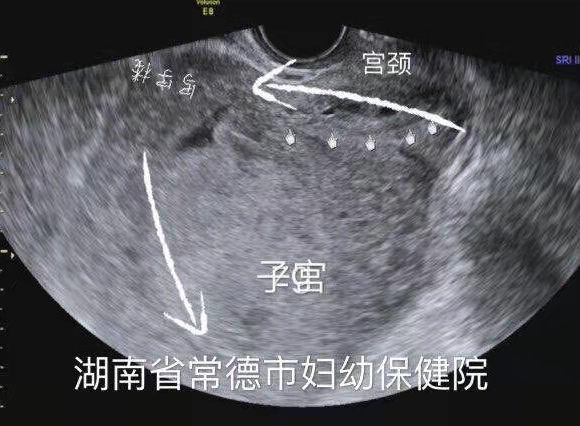

膀胱明显充盈表现细长,后方见妊娠子宫回声

子宫明显后倾后屈,宫颈细长